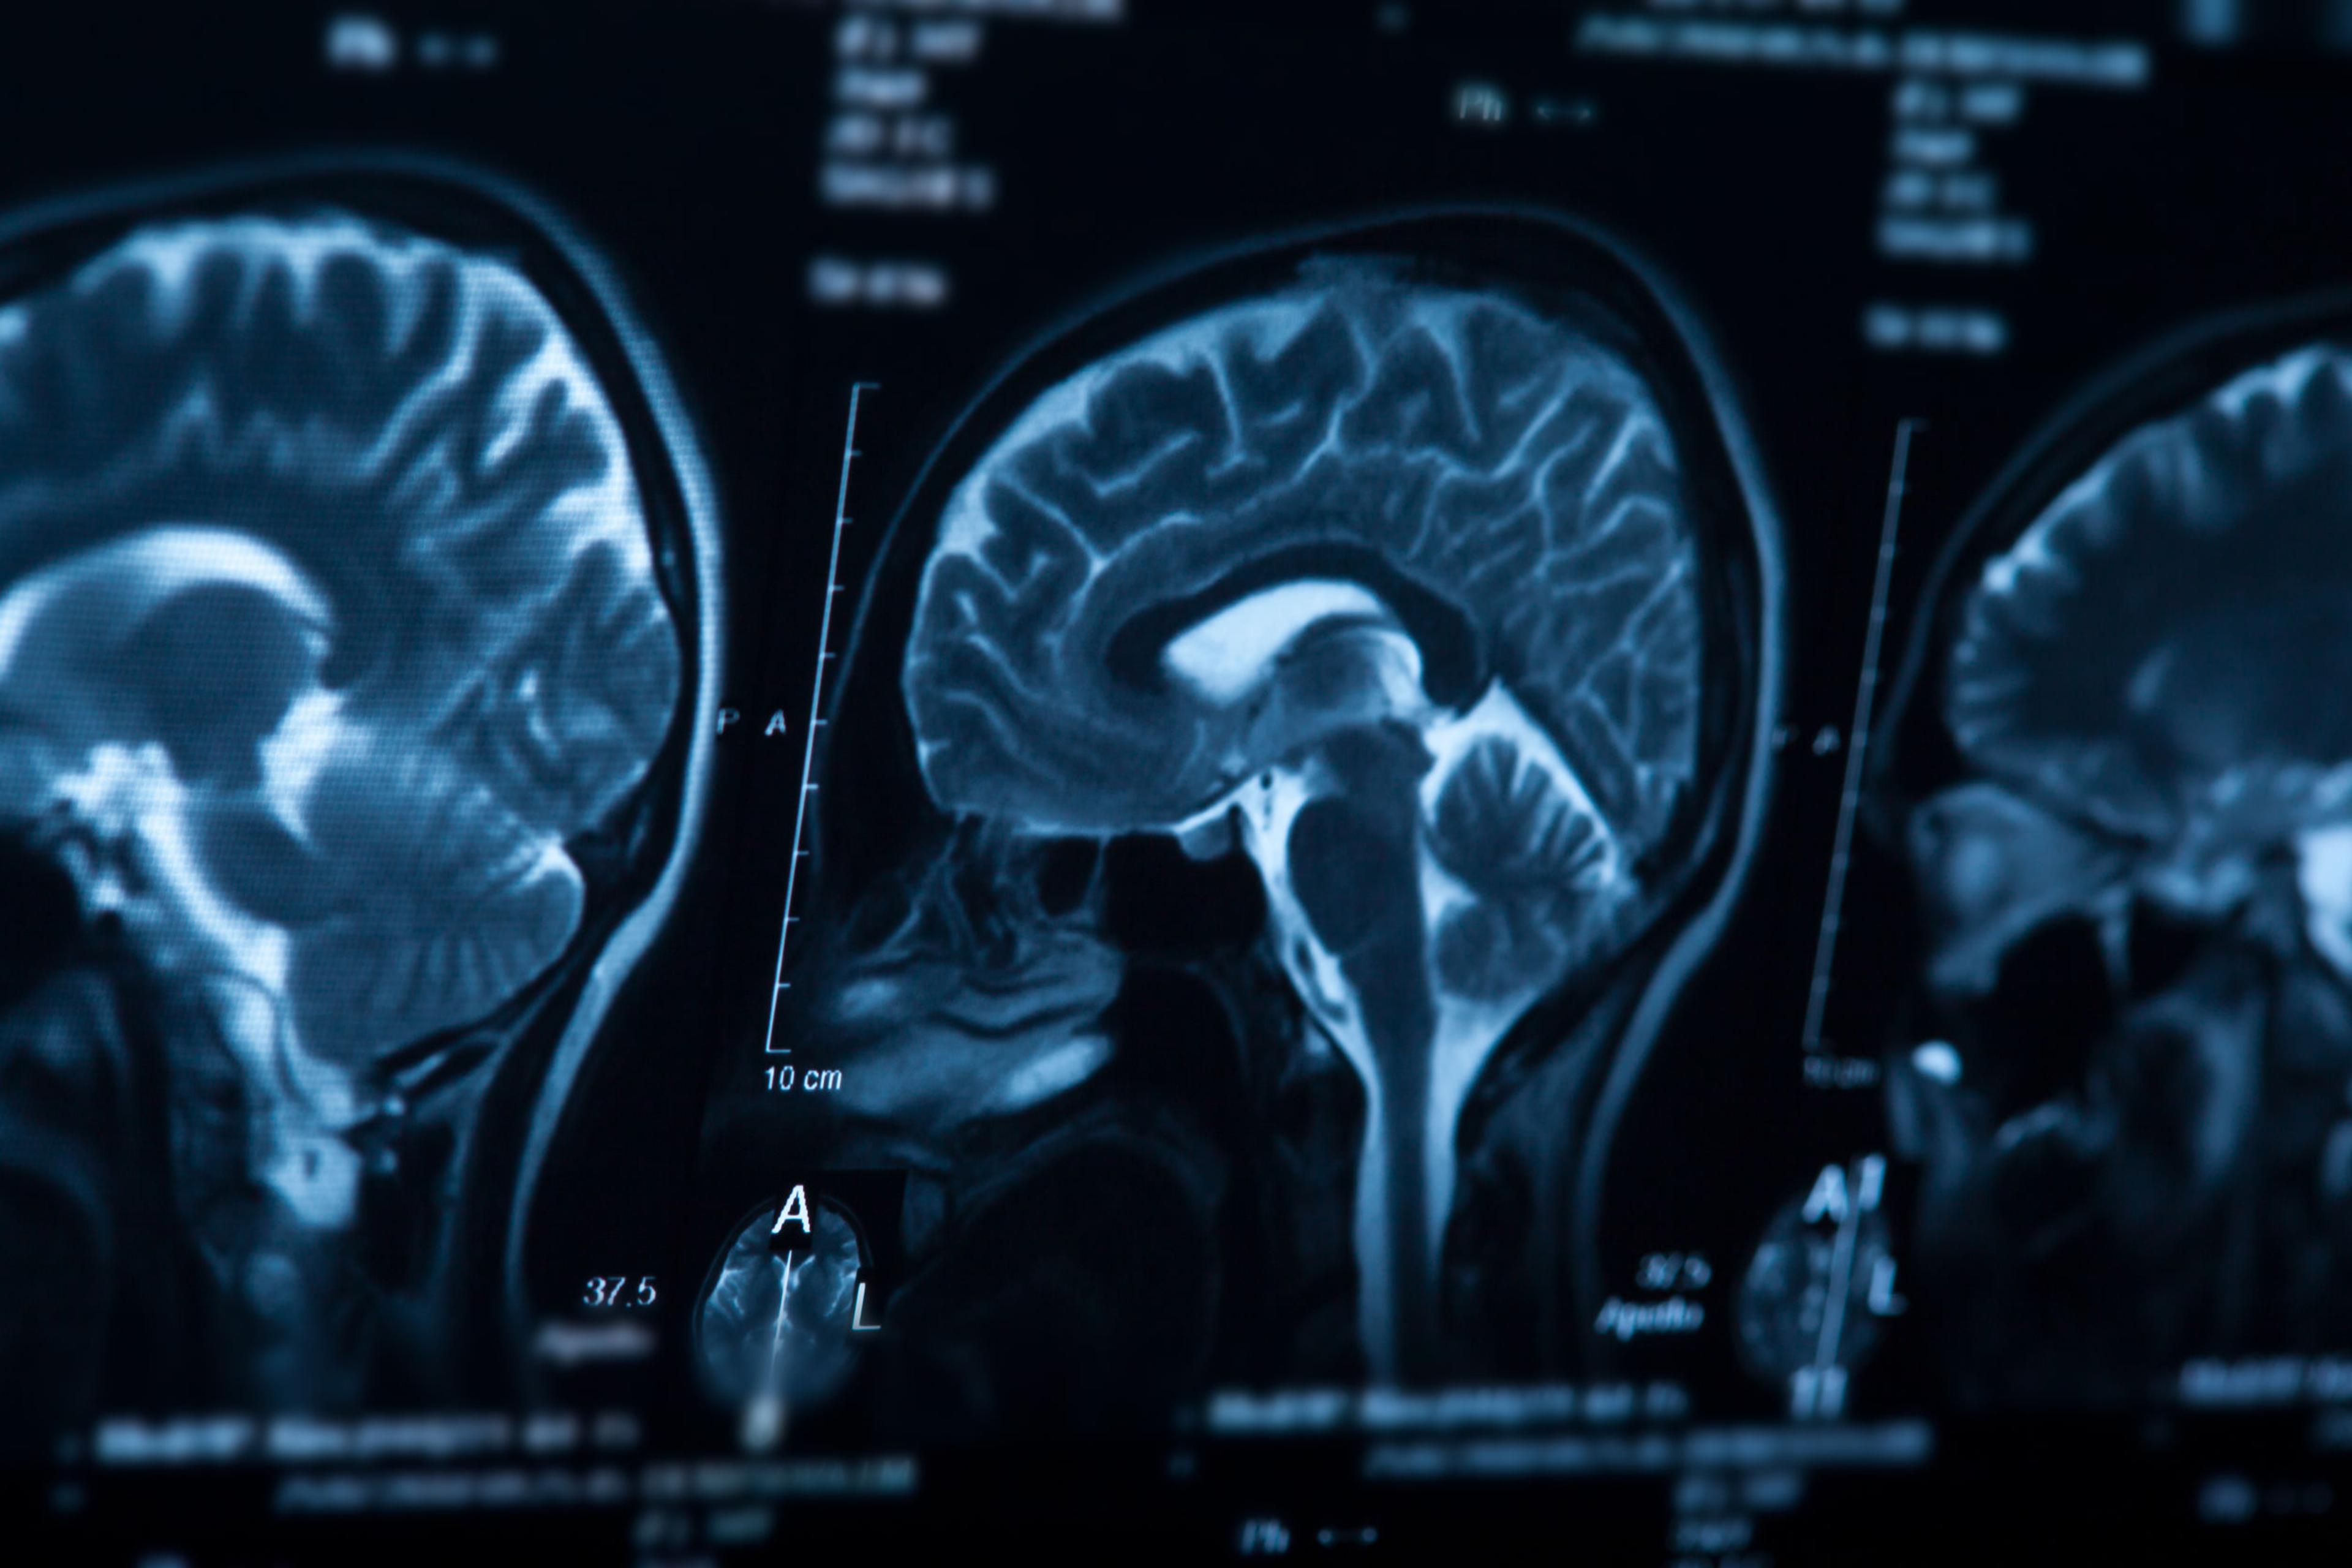

Alzheimer's disease is a progressive brain disorder that destroys memory and thinking skills. ©merydolla @123rf.com

Early diagnosis and intervention can help to improve outcomes for individuals living with Alzheimer’s disease, as well as for their caregivers and families. Currently, the diagnosis of Alzheimer’s disease is made following subjective symptom reporting, cognitive testing, and a series of lab tests that rule out reversible or treatable conditions that can cause cognitive changes. Other testing includes imaging studies such as computerized tomography (CT) scans, magnetic resonance imaging (MRI), and/or positron emission tomography (PET) scans. However, changes in the brain may occur long before clinical symptoms are detected, making early diagnosis of Alzheimer’s disease particularly challenging. Alzheimer’s disease progresses on a spectrum of 3 phases: preclinical, mild cognitive impairment, and then dementia, which is further stratified into mild, moderate, and severe stages. How quickly patients progress through the continuum varies and is influenced by factors including age, environmental factors, genetics, and sex.1